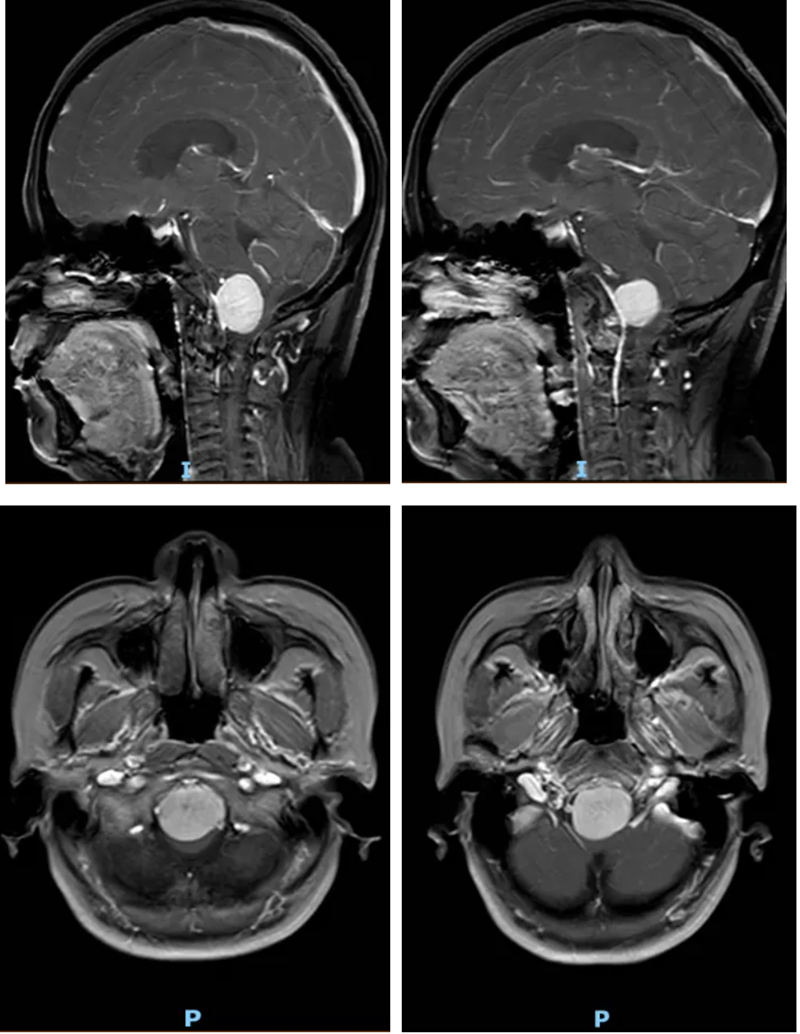

術后復查頭顱CT和MRI結果顯示,李女士腦部的腫瘤被徹底切除,延髓所受壓迫完全解除。術后恢復期間,在神經外科、麻醉科(手術室)、電生理監測團隊、神經重癥及術后護理團隊的多學科協同照料下,李女士恢復順利。她的頭昏、頭痛癥狀徹底消失,肢體肌力明顯改善,未出現任何新發神經功能障礙,目前已逐步恢復正常生活能力。